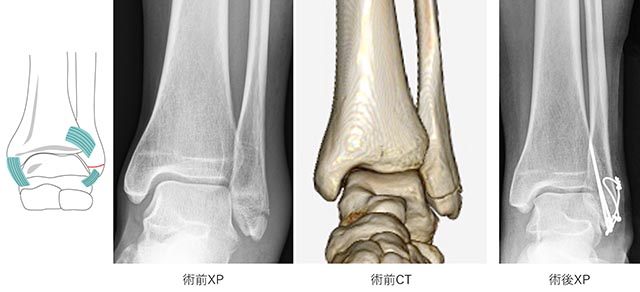

手術の方法は、骨折した部分をもともとの形に整復し、プレートやスクリュー、針金などを用いて固定します(図6−8)。

図6.TypeA骨折